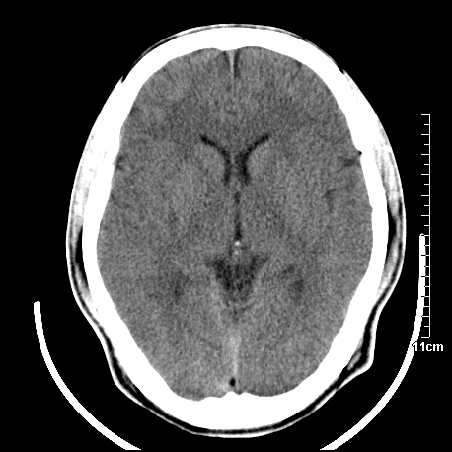

头晕.头痛间断意识恍惚1周 m/21y

4天上述症状加重伴左侧肢体发软,复查ct,

右侧放射冠可见点状低密度,可疑腔隙性梗塞

我当时诊断的是1.右侧底节区脑血栓形成

2.考虑少量蛛网膜下腔出血

3.右侧颞叶低密度区考虑脑血管畸形

因病人拒绝进一步检查,反复做工作后,病人做了腰穿,脑脊液化验显示有红细胞,呈现轻度红色

右侧基底节区低密度灶,建议磁共振检查。